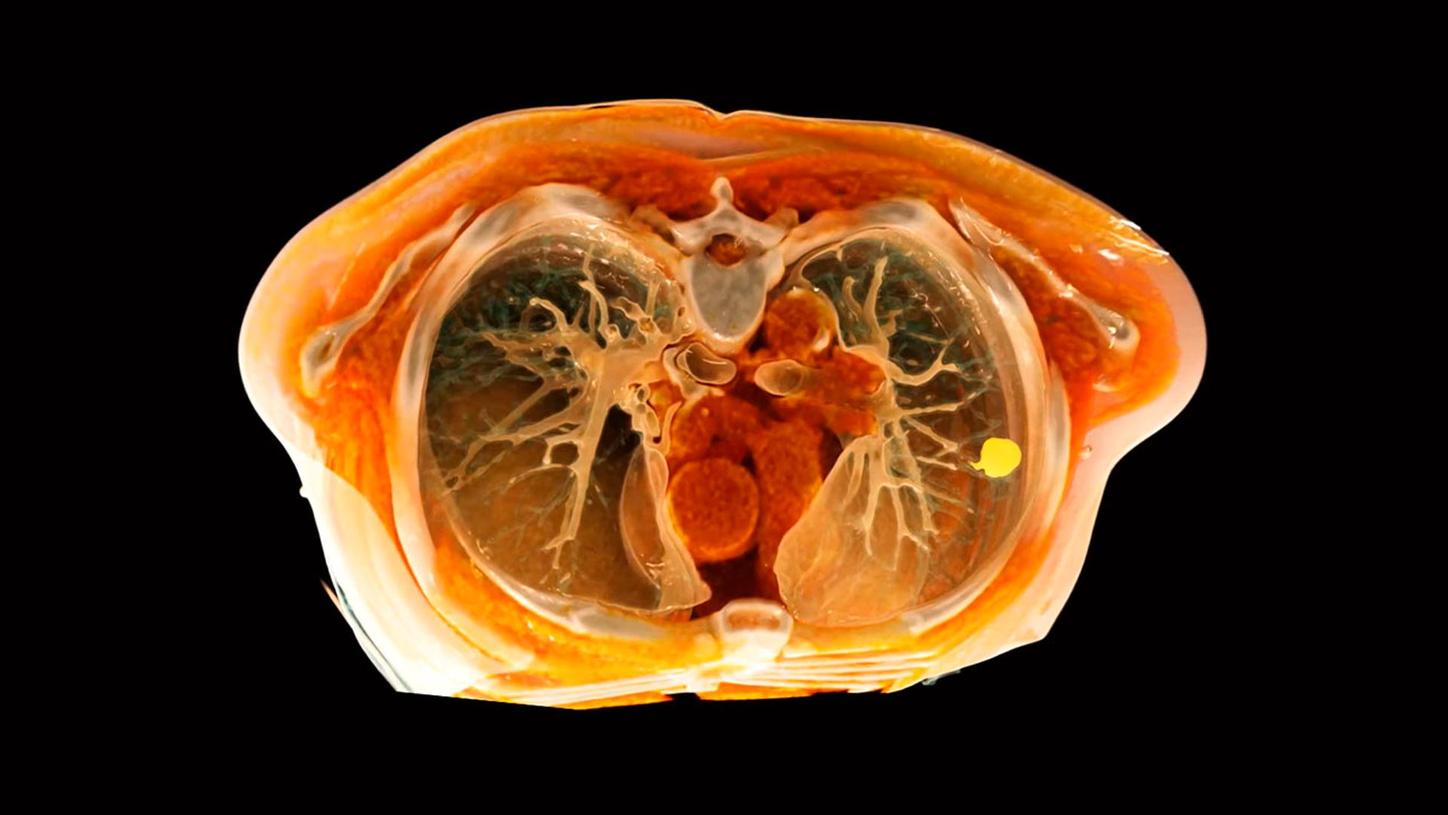

Lung cancer: Imaging of the lungs used for cancer diagnosis

Lung cancer

Early stage lung cancer imposes challenges on therapy because of small targets and the natural deviation between accurate diagnostic findings and the situation during surgery, intervention or radiotherapy2. We provide imaging solutions supporting non- and minimally-invasive lung cancer therapy to face these challenges. Many factors are impacting clinical outcomes. However, our vision is to contribute with our technology to improve survival rates, less complications and a better quality of life of cancer patients.